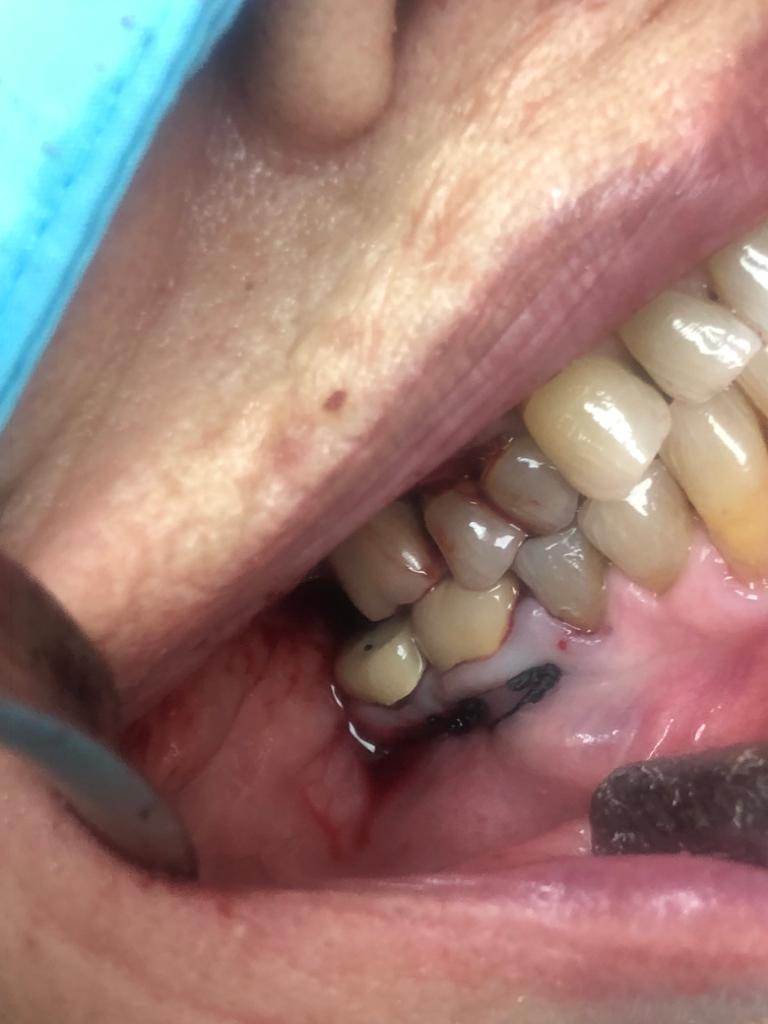

La técnica quirúrgica para este menester es parecida a una apicectomía, pero en lugar de quitar solo el ápice radicular quitamos toda la raíz dental. Así pues lo que se hizo fue extracción de la raíz distal del primer molar y extracción de la raíz mesial del segundo molar. Con lo que la prótesis sigue teniendo dos pilares.

En conclusión, lo que hicimos fue alisar la prótesis por debajo de forma que quede higiénica y por tanto no retenga restos. La técnica quirúrgica quedo muy bien. El tiempo de inflamación de la cara es como si se hubiera hecho la extracción de la muela del juicio, pero una vez se va la inflamación el paciente sigue haciendo vida normal, como el día que se le puso la prótesis.

Lo más importante, es que a los diez días se quitan los puntos y poco a poco se vuelve a la normalidad.

Con la secuencia de imágenes se comprende muy bien la técnica quirúrgica realizada.